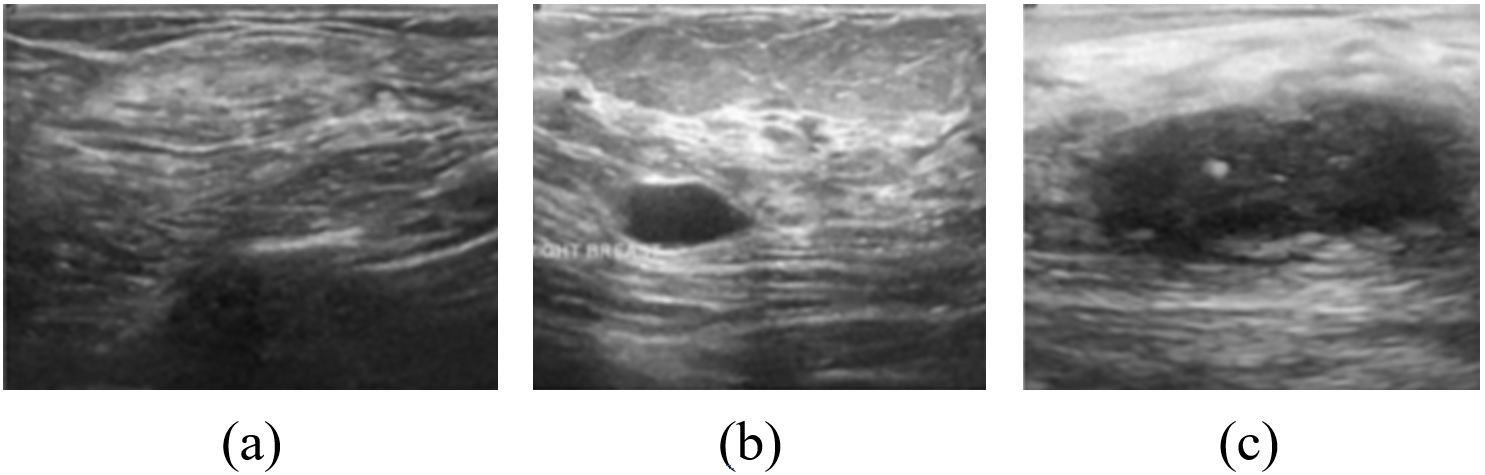

In this research, two breast ultrasound image datasets [25, 26] were considered. The dataset in [25] contains 250 images in which there are two categories: malignant and benign cases. The images in this dataset have different sizes with gray and RGB colors. The minimum and the maximum size of the images are 57×75577557\times 75 and 61×1996119961\times 199 pixels, respectively. The dataset in [26] contains 780 images, in which there are three categories: malignant, benign, and normal cases. These images are collected from 600 women in 2018, and the age range of the women is between 25 and 75 years. The average size of the images in this dataset is 500×500500500500\times 500 pixels. The images in [25, 26] are combined to increase the size of the training and testing dataset. That’s to avoid the overfitting and biases in the training process and to consider the three classes (benign, malignant, and normal) at the output of the neural network. Samples of the ultrasonic images from dataset 1 [25] and dataset 2 [26] are illustrated in Figure 1 and Figure 2 respectively. The class distribution of the images in the two datasets is shown in Table 1.

Figure 2: Samples of the ultrasonic images from the dataset 2: (a) Normal (b) Benign cancer. (c) Malignant cancer.